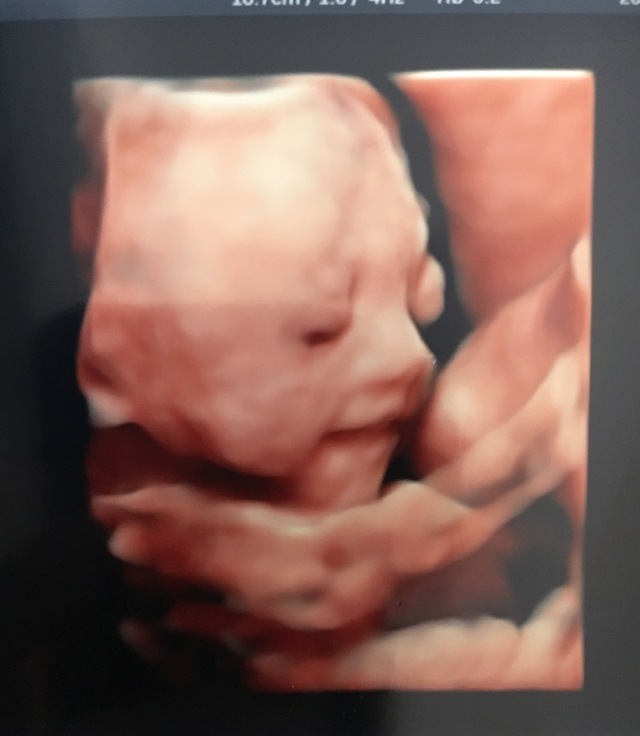

25週4日(25w4d・男の子)|(^^)くえみ さん(26歳)

エコー写真撮影時のエピソード:

先生が必死に顔を私に見せようとしてくれましたが、がなかなか見せてくれない我が子。 やっとちょっと見えたかなーっと思ったけどやっぱり手で顔を隠してる!

「あちゃー、見られちゃってる!恥ずかしい!!」って言ってるみたいでほっこりしたエコー写真です。